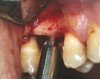

A 53-year-old female was referred for evaluation of a fracture of tooth No. 24. The tooth had been treated endodontically 5 years prior. The radiograph revealed a complete fracture of the tooth involving the crown (Figure 12). Tooth extraction and immediate placement of a an implant that was 10 mm in length and 3.75 in diameter was planned.

At the time of surgery, the tooth was extracted without harvesting any mucosal flap because the implant site was prepared by means of a pilot drill bur (Figure 13) and alternating osteotomes (Figure 14A and Figure 14B). The implant was positioned and showed primary stability. The implant was loaded 2 days after surgery. Then, splinted PFM crowns supported by custom gold abutments were delivered. At 6 months posttreatment, the radiograph revealed no bone resorption and the clinical result was optimal (Figure 15A and Figure 15B).

Figure 13 The drill bur was used to start the implant site preparation.

Figure 14A and Figure 14B Alternating osteotomes were used to prepare the implant site.